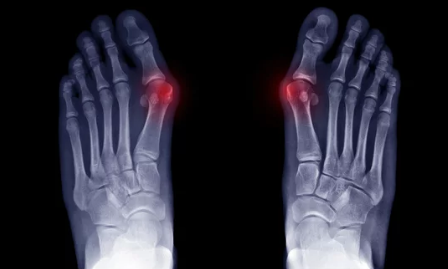

무지외반증(Hallux Valgus)은 엄지발가락이 안쪽으로 휘어지며 발톱이 바깥쪽으로 돌출되는 질환입니다. 이로 인해 발에 불편함을 느끼거나 심한 통증을 유발할 수 있으며, 걷거나 서 있는 동안 큰 어려움을 겪기도 합니다. 특히 여성에서 더 많이 발생하는 이 질환은, 발의 구조적 변형으로 인해 일상생활에 지장을 줄 수 있습니다. 무지외반증을 조기에 발견하고 적절한 치료를 받는 것이 중요합니다. 이번 글에서는 무지외반증의 원인, 증상, 치료 방법, 예방 방법까지 모든 정보를 상세히 다뤄보겠습니다.

(1) 엄지발가락 휨

무지외반증의 가장 흔한 증상은 엄지발가락이 안쪽으로 휘어지는 현상입니다. 엄지발가락이 점차 안쪽으로 휘어져 발톱이 바깥쪽으로 돌출되며, 발가락의 변형이 진행됩니다.